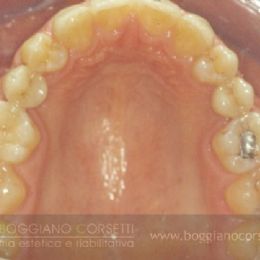

In questa bocca gli incisivi laterali non sono mai nati (agenesia) ed i canini hanno preso il loro posto. E’ rimasto anche uno spazio interincisivo (diastema). I primi premolari sono ruotati e malposizionati e i II premolari permanenti sono mancanti.

Fasi Operatorie dell'Intervento

Come è noto, la forma dei canini ed il loro colore li rende inadatti per armonizzarsi in un sorriso al posto degli incisivi laterali.

Per ovviare a questo problema è stato necessario spostare i canini (soprattutto la loro radice, molto superficiale) all’interno e fargli assumere con l’ortodonzia una posizione più idonea per poter essere poi “camuffati” da incisivi laterali con delle faccette (valutazione da parte del tecnico della forma, per dare l’illusione ottica di ridurre il diametro del canino a quello di un laterale.

Al posto dei premolari mancanti il dr. Boggiano ha inserito degli impianti con la tecnica del carico immediato (vedi menù)

e questo è il risultato finale, il cui successo estetico è dipeso dall’approccio globale a tutta la bocca e dall’attenzione al singolo particolare da parte del nostro team.